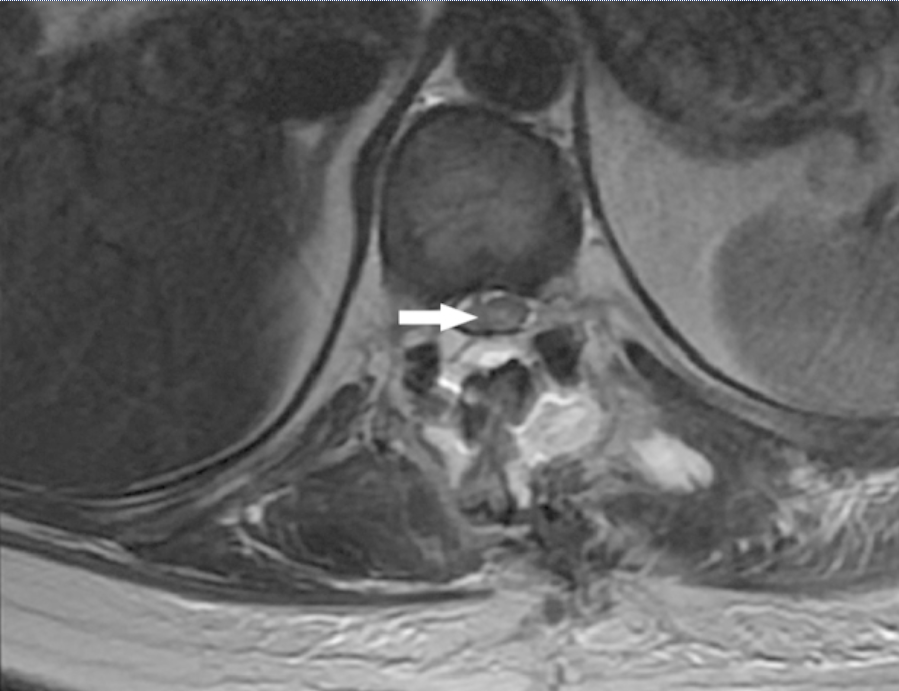

问:脊髓脑膜瘤术后后遗症有哪些? 答:脊髓脑膜瘤较颅内室的发病率相对少见,约占中枢神经系统脑膜瘤的1.2%。脊髓脑膜瘤一般是硬膜内和髓外的。脊...